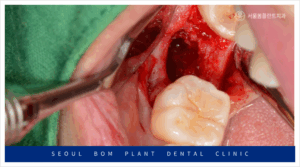

발치 후 3개월이 지난 뒤,

임플란트 식립을 위해 잇몸을 절개하고

골 내부 상태를 확인한 결과,

발치 당시 심한 염증이 있었던 부위가

잇몸뼈 회복이 더디게 이루어져

움푹 패인 상태를 보였습니다.

이렇게 잇몸뼈가 부족한 상태에서

무리하게 임플란트 식립을 하게 되면,

식립한 임플란트가 고정력을 얻지 못하게 되어,

결국 흔들리거나 금세 탈락하는 등의

문제가 발생할 수 있습니다.

오금역치과 서울봄플란트에서는 임플란트 식립 전,

부족한 잇몸뼈를 채우기 위해

다량의 뼈이식을 먼저 진행하였습니다.

뼈이식은 임플란트를 안정적으로 식립하기 위한

필수적인 과정으로, 잇몸뼈가 부족한 경우에

필요한 치료입니다.

뼈이식 후에는 하얀색 막인 흡수성

멤브레인으로 이식한 부위를 덮어주었습니다.